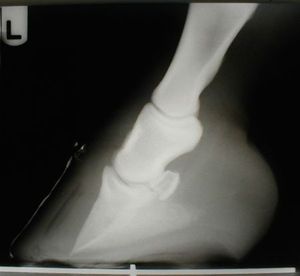

Puncture wounds of the sole in horses can range from simple to complex-even life-threatening-depending on the area of penetration.